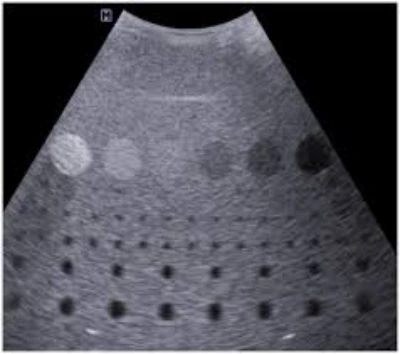

O especialista em aplicação ultrassom atua com conhecimento técnico e experiência na utilização correta do aparelho, assegurando precisão e confiabilidade nos exames.

O especialista em aplicação ultrassom é responsável por operar o equipamento de ultrassom, realizando exames e procedimentos de imagem com precisão e qualidade.

Além disso, ele deve estar apto a identificar possíveis falhas no aparelho, assegurando seu pleno funcionamento.

A interpretação dos resultados obtidos também faz parte de suas atribuições, contribuindo para a elaboração de laudos precisos e confiáveis.